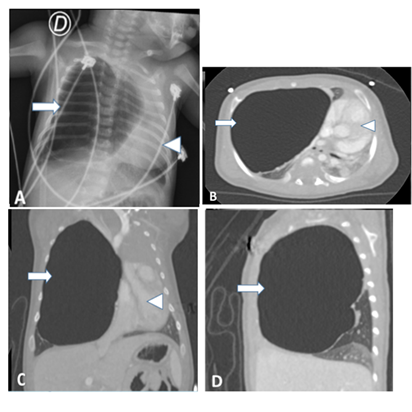

After the first month of life the patient was

admitted in the emergency room with signs of respiratory insufficiency

(tachypnea, subcostal and intercostal retraction, generalized cyanosis),

irritability and difficulty feeding. Chest x-ray revealed an important

radiolucent lesion on the right hemi thorax. The lesion was wall thinned, well

defined and caused important contralateral mediastinal shift. Chest ct with

angiogram exhibited a voluminous cystic mass in the upper lobe of the right

lung, size 81 x 67 x 58mm. The compressive effect of the lesion caused partial

atelectasis of the lower lobe with diffuse increase in its density. There were

signs of air entrapment in the middle lobe and compression of the intermediary

bronchus. There was not systemic vascularity recognized on the ct-angiogram (figure 5).

Figure 5: a. Chest x-ray one month old after birth. Image

shows an air-filled cystic image (arrow) that displaces the mediastinum (arrow

tip) to the left. B, c and d ct scan images with lung window in axial, coronal

and sagittal projections demonstrating an unilocular cystic image with air

content compressing the adjacent lung parenchyma and produces mediastinal

deviation. Intravenous contrast did not show internal or systemic vascularity.